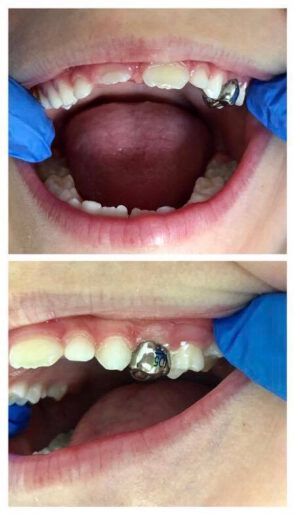

Korony stalowe stosowane są do odbudowy tkanek zębów trzonowych mlecznych. Są uznawane jako jedna z najlepszych form uzupełnień u dzieci.

Wskazaniem do wykonania koron stalowych są przede wszystkim ubytki próchnicowe, które obejmują co najmniej dwie powierzchnie zębów mlecznych, odbudowa zębów pourazowych lub z zaburzeniami rozwojowymi.

Badania naukowe dowodzą, że korony stalowe są najbardziej trwałym uzupełnieniem u dzieci. Odbudowują kształt oraz funkcję zęba mlecznego i pozwalają na jego utrzymanie w jamie ustnej do czasu fizjologicznej wymiany. Korona stalowa ochrania wszystkie powierzchnie zęba mlecznego przed próchnicą. W przeciwieństwie do zwykłego wypełnienia, nie ma konieczności powtórnego leczenia lub wymiany korony przed fizjologicznym wypadnięciem zęba mlecznego, dlatego pozwalają na oszczędność Państwa czasu oraz pieniędzy.

Korony metalowe są już gotowe (prefabrykowane), więc można je założyć podczas jednej wizyty. W trakcie wizyty lekarz dentysta dobierze odpowiedni rozmiar korony, oczyści ząb oraz zacementuje ją na specjalny klej.